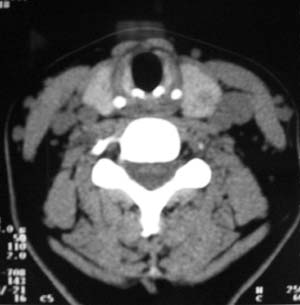

以下是引用zsl6918在2007-8-27 14:40:00的发言:[br]双侧甲状腺多发性低密度占位,边界清晰,密度欠均匀,尤以左侧明显,与周围组织分解清,考虑多发性腺瘤可能性大,不除外结节性甲状腺肿

以下是引用liaizhi在2007-8-27 15:20:00的发言:[br]双侧甲状腺散在多个囊性第密度影,左侧最大一个病灶与正常甲状腺分界尚可,气管受压稍右移。考虑甲状腺瘤的可能性大。

以下是引用zsl6918在2007-8-27 14:40:00的发言:[br]双侧甲状腺多发性低密度占位,边界清晰,密度欠均匀,尤以左侧明显,与周围组织分解清,考虑多发性腺瘤可能性大